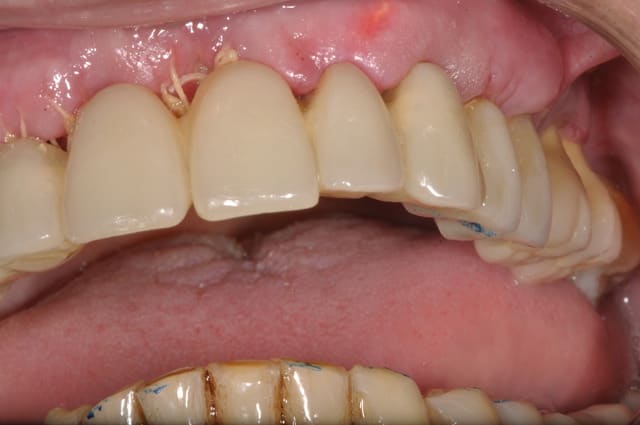

vendredi

extraction implantation mise en charge immédiate

maxillaire

Otp pr  op eyarzp - Eugenol